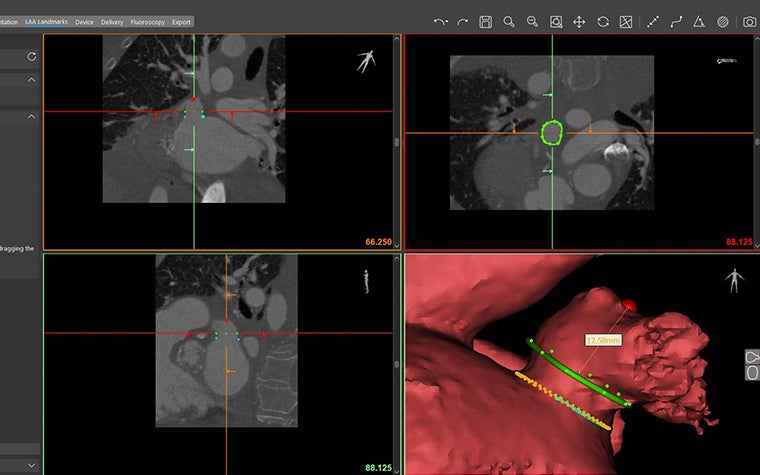

1. Enhanced 3D visualization

Instantly gain an accurate understanding of the LAA anatomy in 3D. You’ll be able to easily assess the relationship between the LAA and surrounding structures with comprehensive visualization and measurements directly in 3D.

2. Landing zone assessment in 3D

You’ll be able to simply indicate the LAA ostium and landing zone on CT or directly on the interactive 3D model and automatically receive accurate area measurements. Visualize and adapt the area in 3D with automatic measurements updates so you can properly assess what you’re going into with the procedure.

3. Automatic appendage depth measurement

Assessing the appendage depth with the intuitive automatic depth measurement tool will be an easy process. Accurately measure the appendage depth by planning in 3D and receiving real-time, updated depth measurements as you adjust your planning.